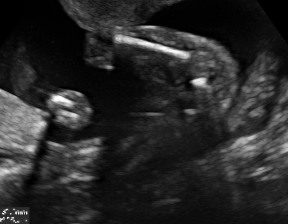

| 4CH | Abdominal | Femur | Lips | LVOT | |

| SF | |||||

| SC | ![]() |

![]() |

We demonstrate the practical applicability of our method on a challenging medical application, the classification of standardized fetal ultrasound (US) views during prenatal screening. In many countries, US imaging is clinical routine for prenatal health care. The classification of standardized views is important for a consistent, cross-institutional identification of possible abnormalities [47]. Early detection of pathological development can inform following treatment and delivery options [55, 25]. DNNs have shown promising performance to support this task [2]. However, ultrasound images are often hard to interpreted [40]. Anatomical structures have inconsistent appearance [2] and contain different orientations and shapes of anatomical landmarks [1]. Labeled training data is often insufficient as annotating medical images requires significant expertise and is prohibitively expensive in both time and labor. Manifestation of acoustic shadows [17, 44] as shown in Fig. 2(a) as well as different imaging devices as shown in Fig. 2(b) can lead to a domain shift problem for vanilla DNN classifiers. Exploring domain adaptation in fetal US enables DNN classifiers to be effectively utilized on a wider range, which supports identification of abnormalities from varying data sources. This can benefit prenatal healthcare.

We evaluate the proposed method on two fetal US standard plane classification tasks, where the domain shifts are respectively caused by shadow artifacts (Fig. 2(a)) and different image acquisition devices (Fig. 2(b)). For both tasks, images from source and target domains are unpaired and collected independently. We show the key results in the main paper and detailed implementation, network architectures as well as more results in the supplemental Appendix.

The fetal US dataset consists of 2D fetal US images sampled from 2694 2D US examinations with gestational ages between weeks (iFIND Project 555http://www.ifindproject.com/ ). Eight different US systems of identical make and model (GE Voluson E8) were used for the acquisitions to eliminate as many unknown image acquisition parameters as possible. Six different anatomical standard plane locations have been selected by an experienced sonographer, including Four Chamber View (4CH), Abdominal, Femur, Lips, Left Ventricular Outflow Tract (LVOT) and Right Ventricular Outflow Tract (RVOT). The images have additionally been classified by an expert observer as shadow-containing or shadow-free. In this experiment, the source domain contains shadow-free images (see Fig. 2 (b) SF) while the target domain has shadow-containing images from less favorable imaging conditions (see Fig. 2 (b) SC). Training data consists of all six standard planes from the source domain as well as Abdominal, LVOT and RVOT from the target domain. We aim to separate anatomical features (categorical features) and shadow artifacts features (domain features) to obtain generalized anatomical features for achieving high performance of standard plane classification on (4CH, Femur and Lips from target domain). Here, contains 4CH, Abdominal, Femur, Lips, LVOT and RVOT from the source domain and contains Abdominal, LVOT and RVOT from the target domain. Hyper-parameters to in Eq. 11 are for the proposed MIDNet model and is additionally for MIDNet+.